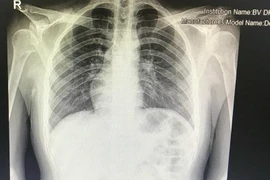

Hy hữu: Cô gái 20 tuổi có phủ tạng đảo ngược, tim và dạ dày nằm bên phải